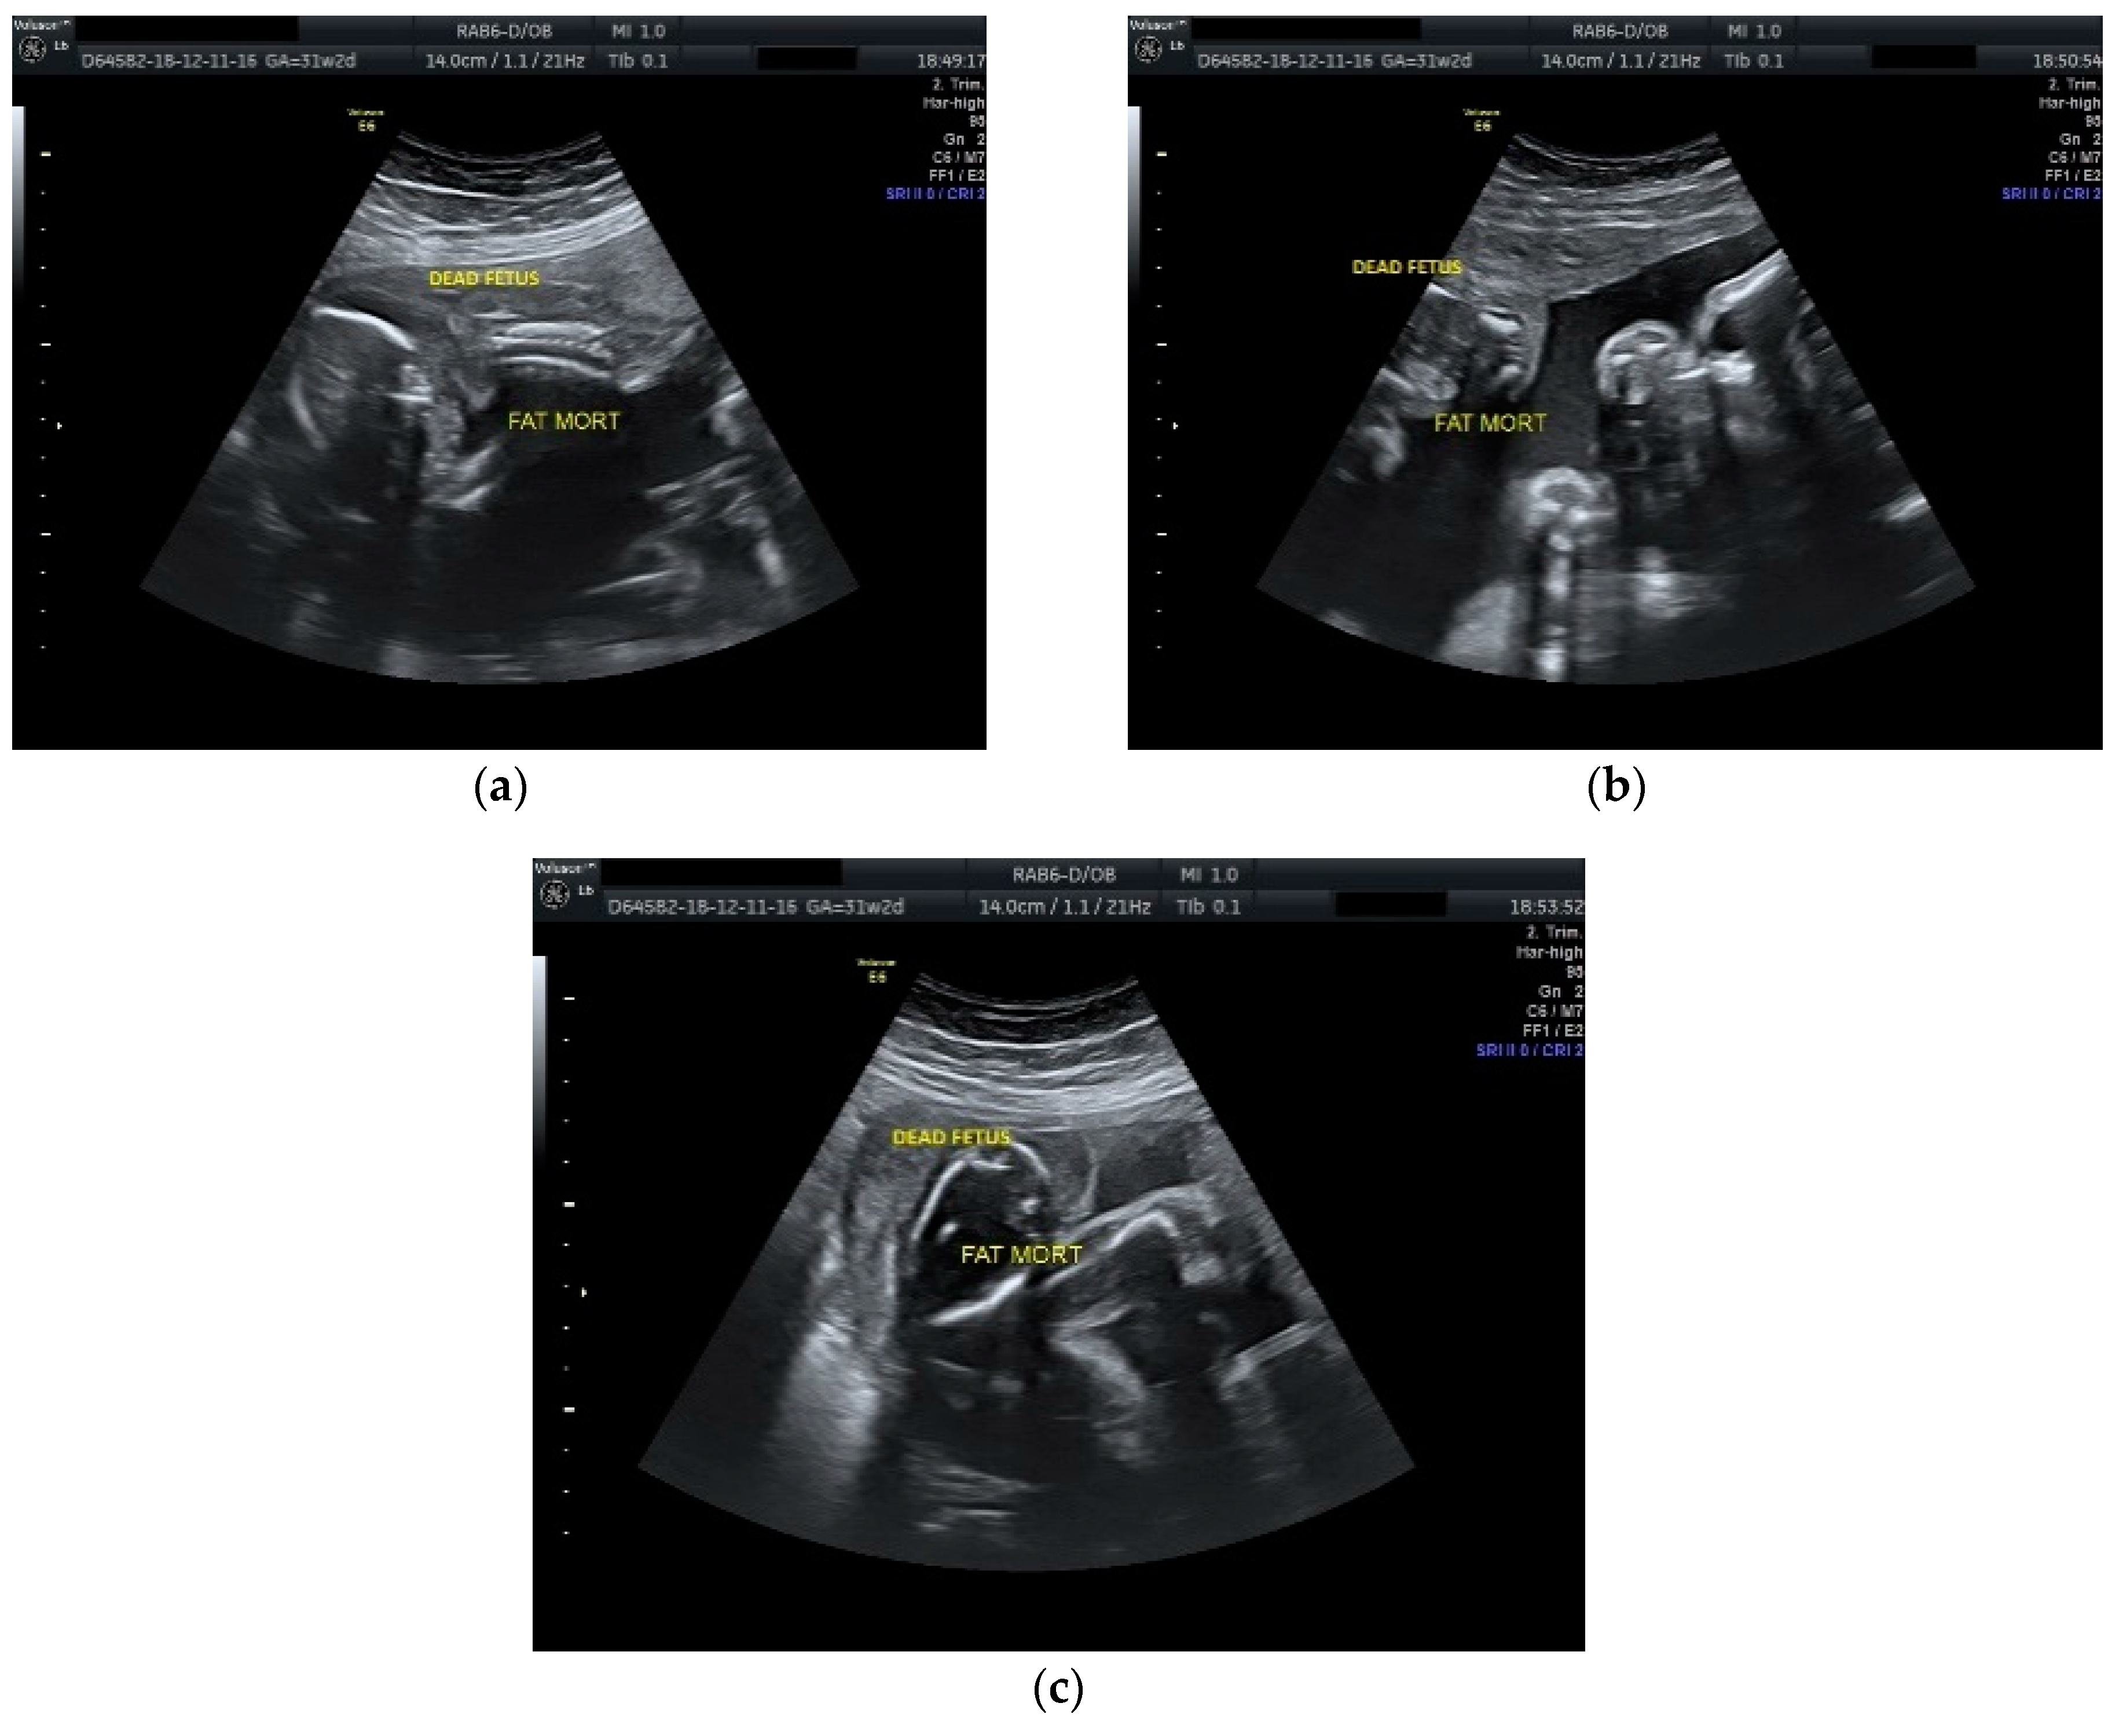

The case was managed conservatively with regular monitoring of the maternal coagulation profile, along with intensive fetal surveillance for the surviving twin (Figure 2 and Figure 3).

Figure 3.

Ultrasound scan performed at 31 weeks and 2 days of gestation: (a), (b), (c) dead fetus with consistent plastic changes along with normal growing fetus with normal amniotic fluid.